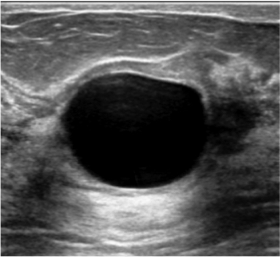

A ultrassonografia pode ser usada de maneira complementar (e não substitutiva) à mamografia, principalmente quando a mama for densa, ou seja, quando a composição da mama apresentar mais glândula que gordura.

- o rastreamento complementar com ultrassonografia deve ser incluído sempre que a mama da mulher for densa;

O achado mais comum na ultrassonografia das mamas é o cisto mamário. Cistos são dilatações saculares repletas de líquido, benignos na enorme maioria dos casos. Normalmente são múltiplos e bilaterais, esparsos no parênquima mamário. O cisto pode ser palpável e, nesse caso, a paciente sentirá um caroço na mama, que deve ser avaliado através da ultrassonografia a fim de comprovar a sua natureza cística (ao invés de sólida).

Os cistos são uma importante causa de dor nas mamas, já que geram compressão do tecido em torno e possivelmente até uma discreta inflamação, mas isso não deve ser um motivo de preocupação pois não reflete risco de câncer. Os cistos não precisam, portanto, ser acompanhados; eles aparecem e somem, podendo retornar ou não, crescer ou diminuir, sem relevância clínica. São mais comuns na idade adulta pré-menopausa já que sofrem influência do ciclo hormonal, mas podem ocorrer também após a menopausa, principalmente se a mulher fizer uso de medicação hormonal.

Não há necessidade de tratamento específico, a menos que atinja um volume grande e gere muito desconforto. Nesse caso, a critério do seu médico, pode-se proceder uma punção com esvaziamento do mesmo a fim de aliviar os sintomas.